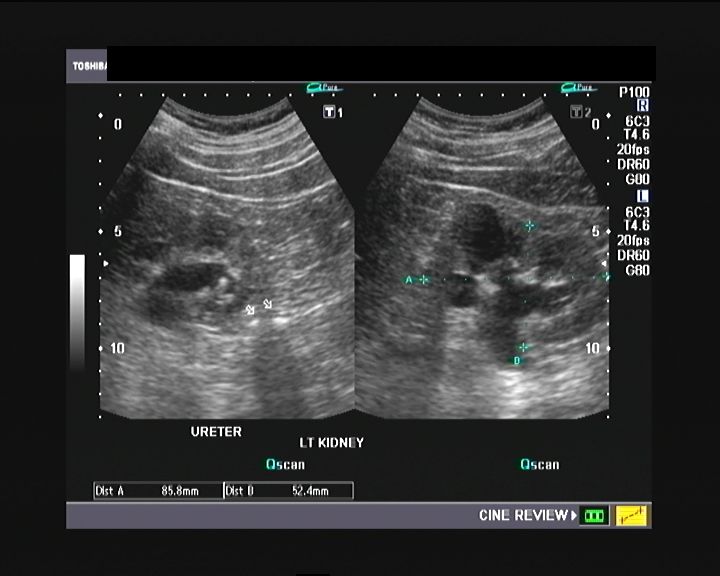

This was a case of left ureteric/ ureteral calculi with resultant hydronephrosis of the left kidney. Fortunately the calculi were in the upper left ureter and hence well visible. Mid ureteral stones can often be difficult to visualize.

Left kidney and left ureter with stones visible in this ultrasound image:

Ultrasound image of the left ureter with 2 calculi seen in the upper part: